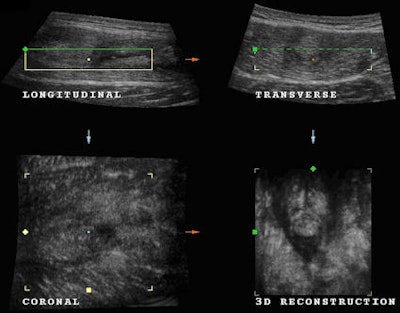

A new volume acquisition was obtained and studied to perform a detailed examination of the condition of the muscle and assist in a complete assessment of the patient's condition before putting the muscle under new strain. The volume acquisition obtained demonstrating the condition of the muscle is shown below (Fig. 5 and 6).

Fig. 5: Multiplanar imaging shows absorption of some of the hematoma but demonstrates the presence of the muscle tear.

Fig. 6: 3D reconstruction (enlarged image) confirming the continued presence of the muscle tear and hematoma.Healing of the tear appears as irregular hyperechoic tissue located distal to the severed muscle due to local scarring tissue. Volume loss and fatty infiltration of the injured rectus femoris reflecting post-traumatic atrophy may become evident. It is evident in this case that the muscle requires further time to heal, and the patient was advised to continue resting.

There is evidence of reabsorption of the hematoma and coagulated material that were present on the original volume acquisition. There was less fluid surrounding the torn muscle on the follow-up scan compared with the original scan, and it is clearly evident that the healing process requires more time. However, classical signs of irregular hyperechoic muscle tissue that is present with the healing process are absent. This patient did not visit our institute for any additional follow-up scans.